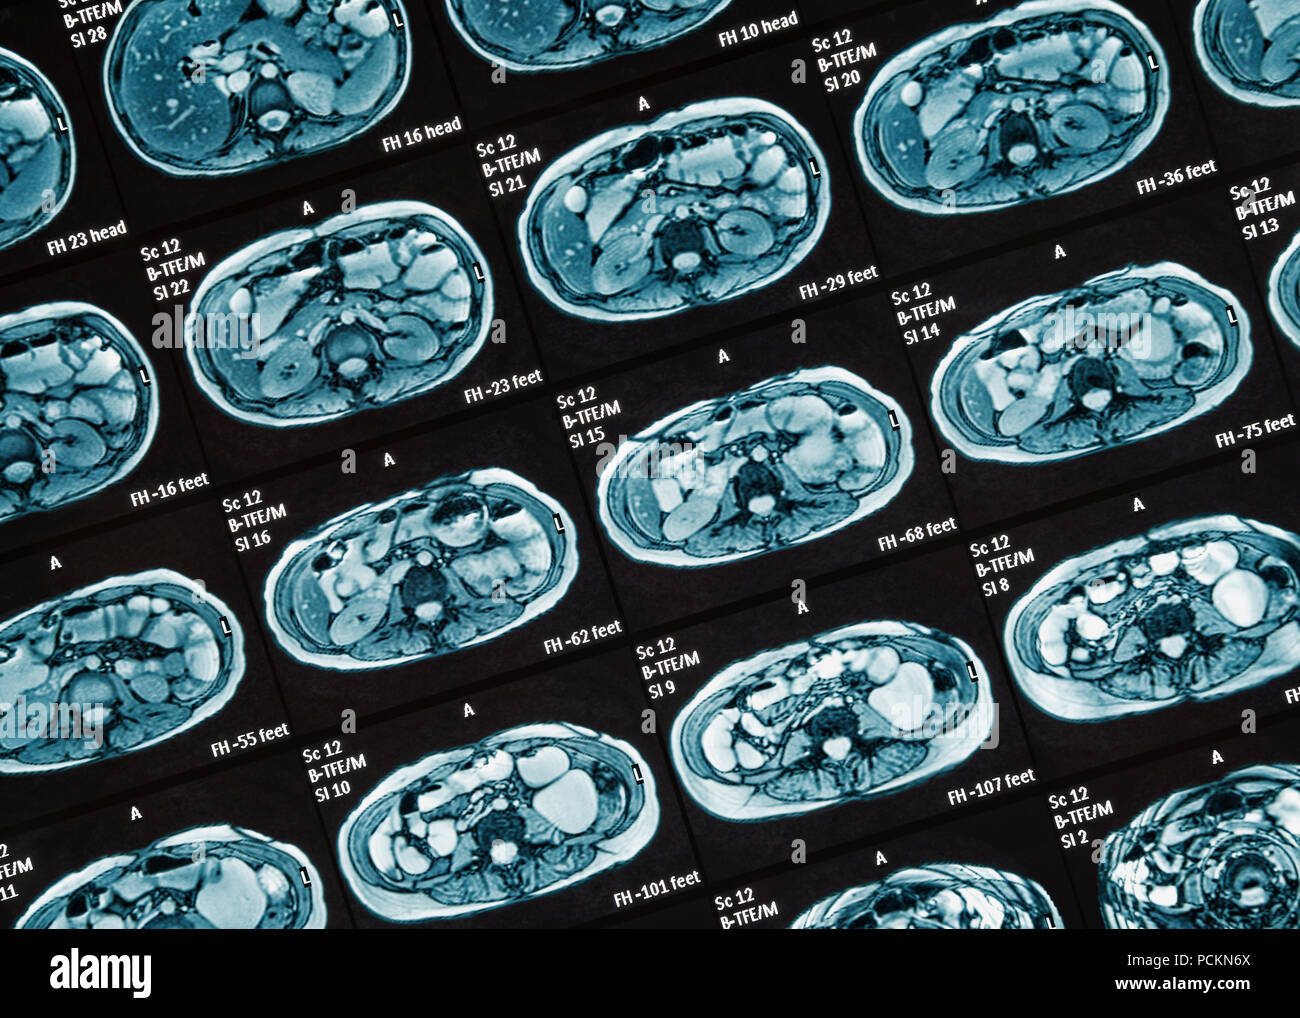

MRI Scan. MR Enterography of the small intestine a noninvasive medical test used to diagnose medical conditions of the bowels, like Crohn's disease Stock Photohttps://www.alamy.com/image-license-details/?v=1https://www.alamy.com/mri-scan-mr-enterography-of-the-small-intestine-a-noninvasive-medical-test-used-to-diagnose-medical-conditions-of-the-bowels-like-crohns-disease-image214221649.html

MRI Scan. MR Enterography of the small intestine a noninvasive medical test used to diagnose medical conditions of the bowels, like Crohn's disease Stock Photohttps://www.alamy.com/image-license-details/?v=1https://www.alamy.com/mri-scan-mr-enterography-of-the-small-intestine-a-noninvasive-medical-test-used-to-diagnose-medical-conditions-of-the-bowels-like-crohns-disease-image214221649.htmlRFPCEHW5–MRI Scan. MR Enterography of the small intestine a noninvasive medical test used to diagnose medical conditions of the bowels, like Crohn's disease

MRI Scan, Close Up. MR Enterography of the small intestine a noninvasive medical test used to diagnose medical conditions of the bowels, like Crohn's Stock Photohttps://www.alamy.com/image-license-details/?v=1https://www.alamy.com/mri-scan-close-up-mr-enterography-of-the-small-intestine-a-noninvasive-medical-test-used-to-diagnose-medical-conditions-of-the-bowels-like-crohns-image214334034.html

MRI Scan, Close Up. MR Enterography of the small intestine a noninvasive medical test used to diagnose medical conditions of the bowels, like Crohn's Stock Photohttps://www.alamy.com/image-license-details/?v=1https://www.alamy.com/mri-scan-close-up-mr-enterography-of-the-small-intestine-a-noninvasive-medical-test-used-to-diagnose-medical-conditions-of-the-bowels-like-crohns-image214334034.htmlRFPCKN6X–MRI Scan, Close Up. MR Enterography of the small intestine a noninvasive medical test used to diagnose medical conditions of the bowels, like Crohn's